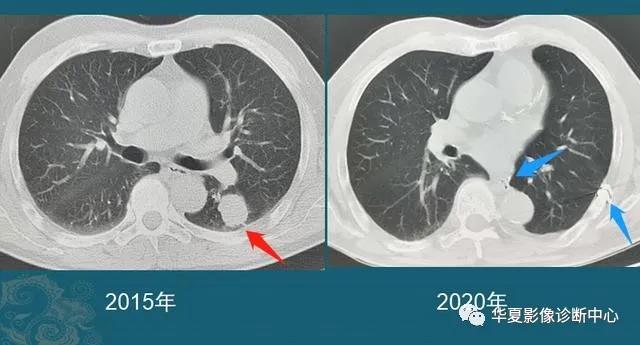

豪大夫每年都能发现很多从肺小结节长大的肺癌,挑出两个速度最快的分享一下:

这位病人2016年体检还是正常的,2017年查出一个3mm的肺结节,用了两年半时间,增长到>1cm,手术病理是肺腺癌。

注意:这几乎是最快的一类的,很少见!所以高危人群推荐每年胸部体检一次是有益的。